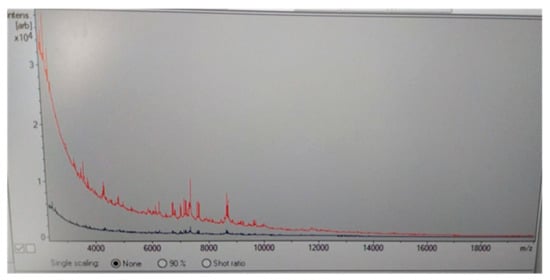

Two days later, the serological diagnosis was confirmed by broth microdilution plates of blood cultures coming back positive for C. neoformans with a high sensitivity to Amphotericin B (minimum inhibitory concentration, MIC: 0.5 μg/mL), Posaconazole (MIC: 0.25 µg/mL), Voriconazole (MIC: 0.25 µg/mL), and Itraconazole (MIC: 0.125 µg/mL) (Figure 2). The detection of C. neoformans was performed using the Maldi toff (Becton Dickinson, Four Oaks, NC 27524, USA) system, the automatic system for microbial identification using mass spectrometry (Figure 2), while the VitekS2 and out the Micronaut-AM system (Merlin broth test in microdilution system) was used for the sensitivity test (Figure 3 and Table 2).

Figure 2.

Maldi Toff spectrometry of Cryptococcus neoformans colony (red line) respect to control line (blue line).